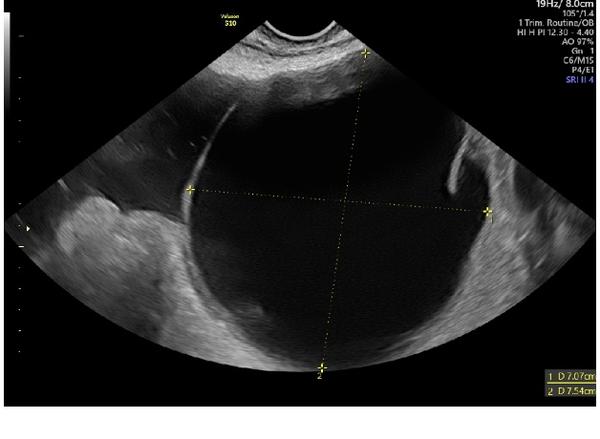

Mela jsem pridat vice informaci, pardon. Jsem po ivf, 2 embrya. Krevni test pozitivni, ale na ultrazvuku si nejsou jisti, zda neco vidi, krom 8cm cysty. Zkousim, zda nekdo nevidi neco vic. A ta cysta mi prijde desiva, take boli.

Takže to nahoře je cysta 😳😳

Ta cysta nemusí být vždy problém. K tomu Vám nějak něco blíže řekli? Když je bolestivá...